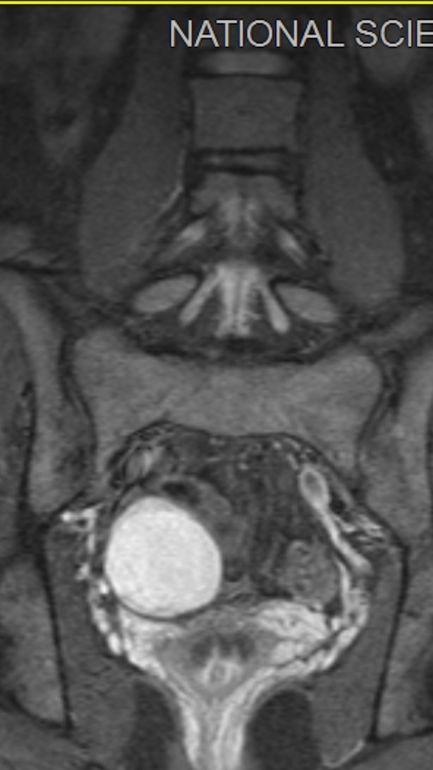

С подозрением на спондилит отправили на МРТ суставов/сочленений (крестец, копчик, таз), а там на нескольких кадрах белый шар объёмом 5.2×4.5×4.2 см.

Собственно, на эту сферу я и думать не могла. Может кто подскажет, что это может быть? Прикреплю одну из фото с МРТ.

Два кадра в разном режиме.